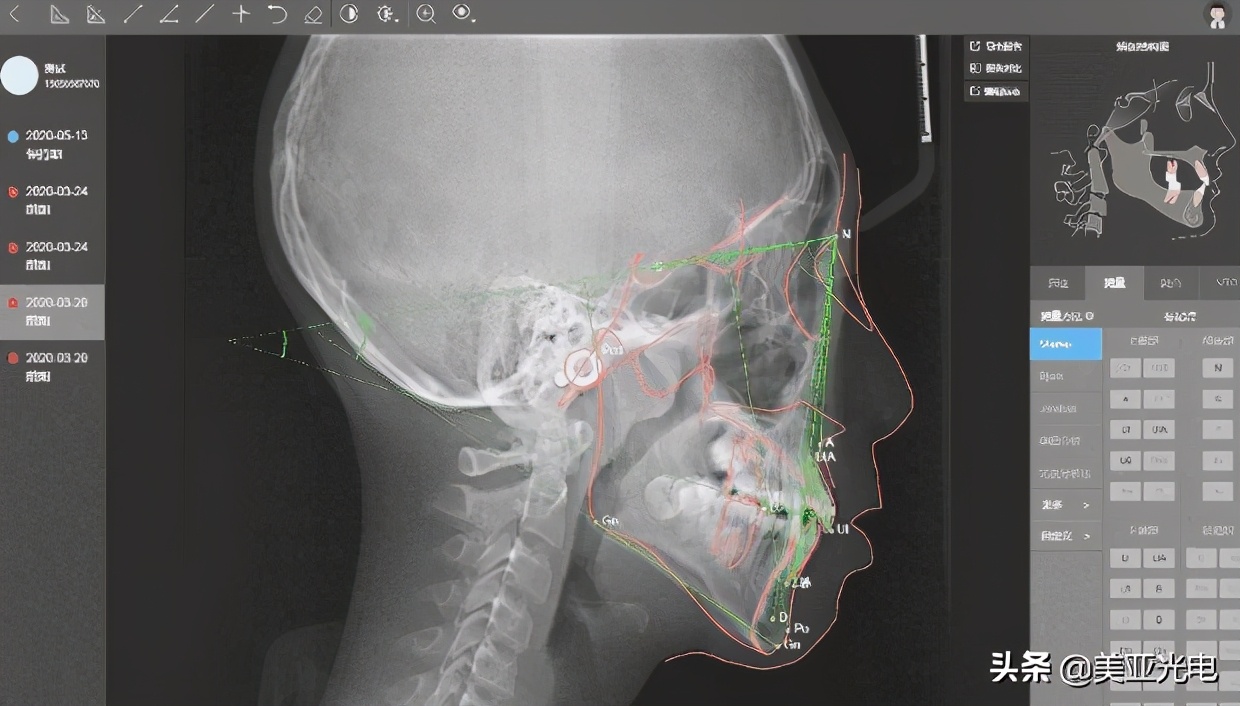

美亚超脑AI正畸分析系统已实现自动描迹、智能测量分析(平均准确率可达98.3%)、一键生成测量分析报告、自动融合侧位照片(人脸*位器定**定位准确度可达98%)、可视化矫正模拟、电子病历管理等功能。

▲支持多种头影测量分析方法